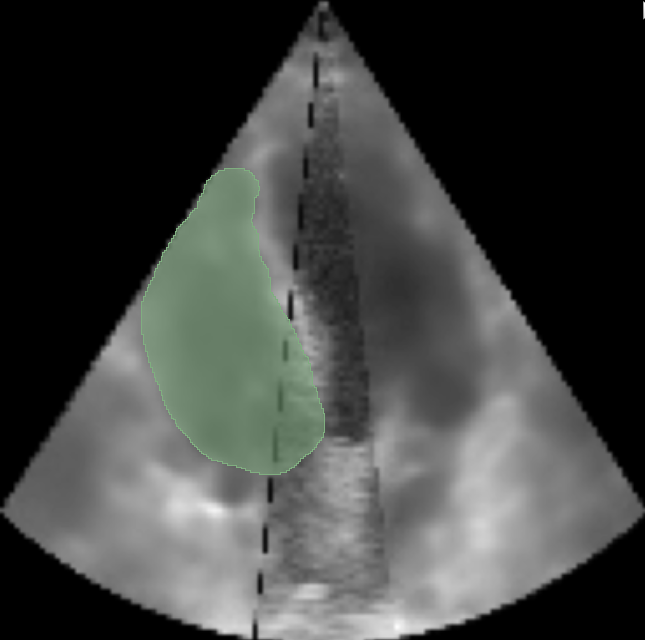

In our experimental setup, both the original and the artificially generated echocardiograms were manually annotated to obtain segmentation masks. This process allowed for precise comparison of RV volumes, assessing the efficacy and accuracy of GAN-based outpainting in reproducing anatomically coherent extensions of the cardiac structures. By comparison of the RV volumes derived from the conventional and outpainted echocardiograms, this experiment aims to validate the potential of echoGANs in overcoming the intrinsic limitations of current echocardiography practices. Comparison of segmentation for RV on original and on outpainted image is in Fig. 5 and Fig. 5.

Refer to caption

Figure 4: Segmentation over Right Ventricle for GT 4CH view with

Figure 5: Segmentation of outpainted RV with 80 degrees cut for the same 4CH view